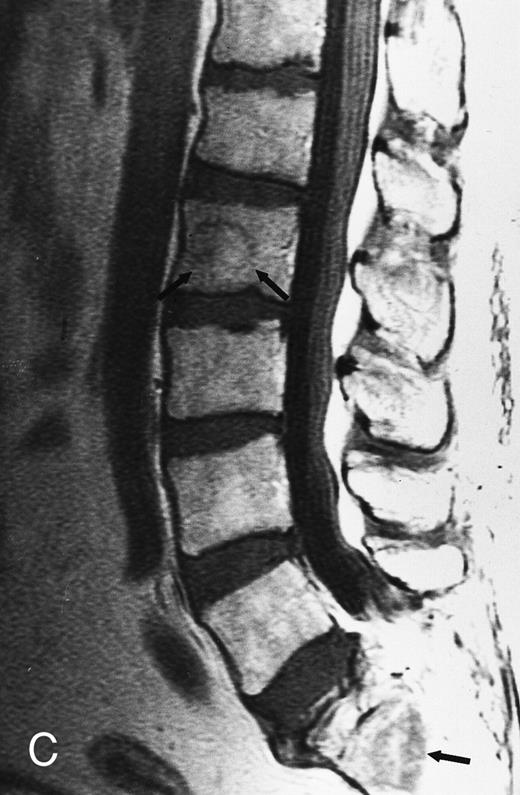

T1-weighted (500/11, TR/TE) sagittal MR images of the lumbosacral spine in a 45-year-old woman before (A) and 40 days after (B) bone marrow transplantation for multiple myeloma. There is a diffuse MR pattern of marrow involvement in (A) (bone marrow plasma cells, 50%; monoclonal protein, 6.0 g/dL). On the posttreatment image, there is definite reinstitution of fatty marrow in the spine and, in particular, around the basivertebral veins, in keeping with partial response to treatment (bone marrow plasma cells, 0.5%; monoclonal protein, 1.6 g/dL).